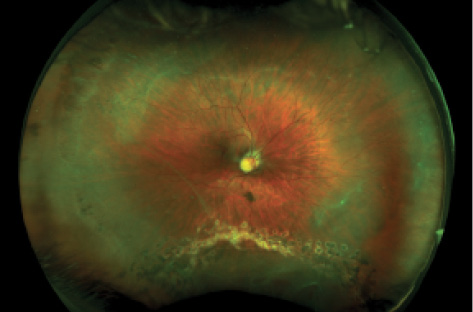

Ultrawide-field imaging enables us to record retinal images for diagnosis and follow-up in both cooperative and uncooperative infants. In our clinic we capture anterior segment and fundus images with the RetCam3 Ophthalmic Imaging System (Natus Medical) and the Daytona digital, nonmydriatic, ultra-widefield scanning laser ophthalmoscope (Optos). We have recently incorporated some newer equipment, such as the PanoCam (Visunex Medical Systems) and ICON (Phoenix Clinical) retinal cameras, into our practice. Some of these devices can capture fluorescein and indocyanine green angiography images (Figures 1 and 2). They can also document the clinical picture and provide specific data about disease progression before and after surgery.7,8

Figure 1. Daytona image of the eye of a 13-year-old boy referred to Bascom Palmer Eye Institute with a history of spontaneously regressed ROP. He was born at 26 weeks and had been treated with barricade laser around a localized inferior retinal detachment. He was closely observed with the aid of ultra-widefield imaging. The image shows 360° peripheral lattice degeneration. After 2 years of follow-up, the patient’s best corrected visual acuity was 20/20, and the inferior detachment remained stable.